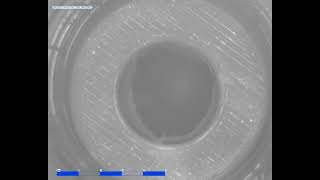

A polymeric heart valve prototype in the pulse duplicator video

A polymeric heart valve prototype in the pulse duplicator

A polymeric heart valve prototype in the pulse duplicator Polymeric Heart Valve in the Pulse Duplicator System

A polymeric heart valve prototype in the pulse duplicator

A polymeric heart valve prototype in the pulse duplicator Polymeric Heart Valve in the Pulse Duplicator System